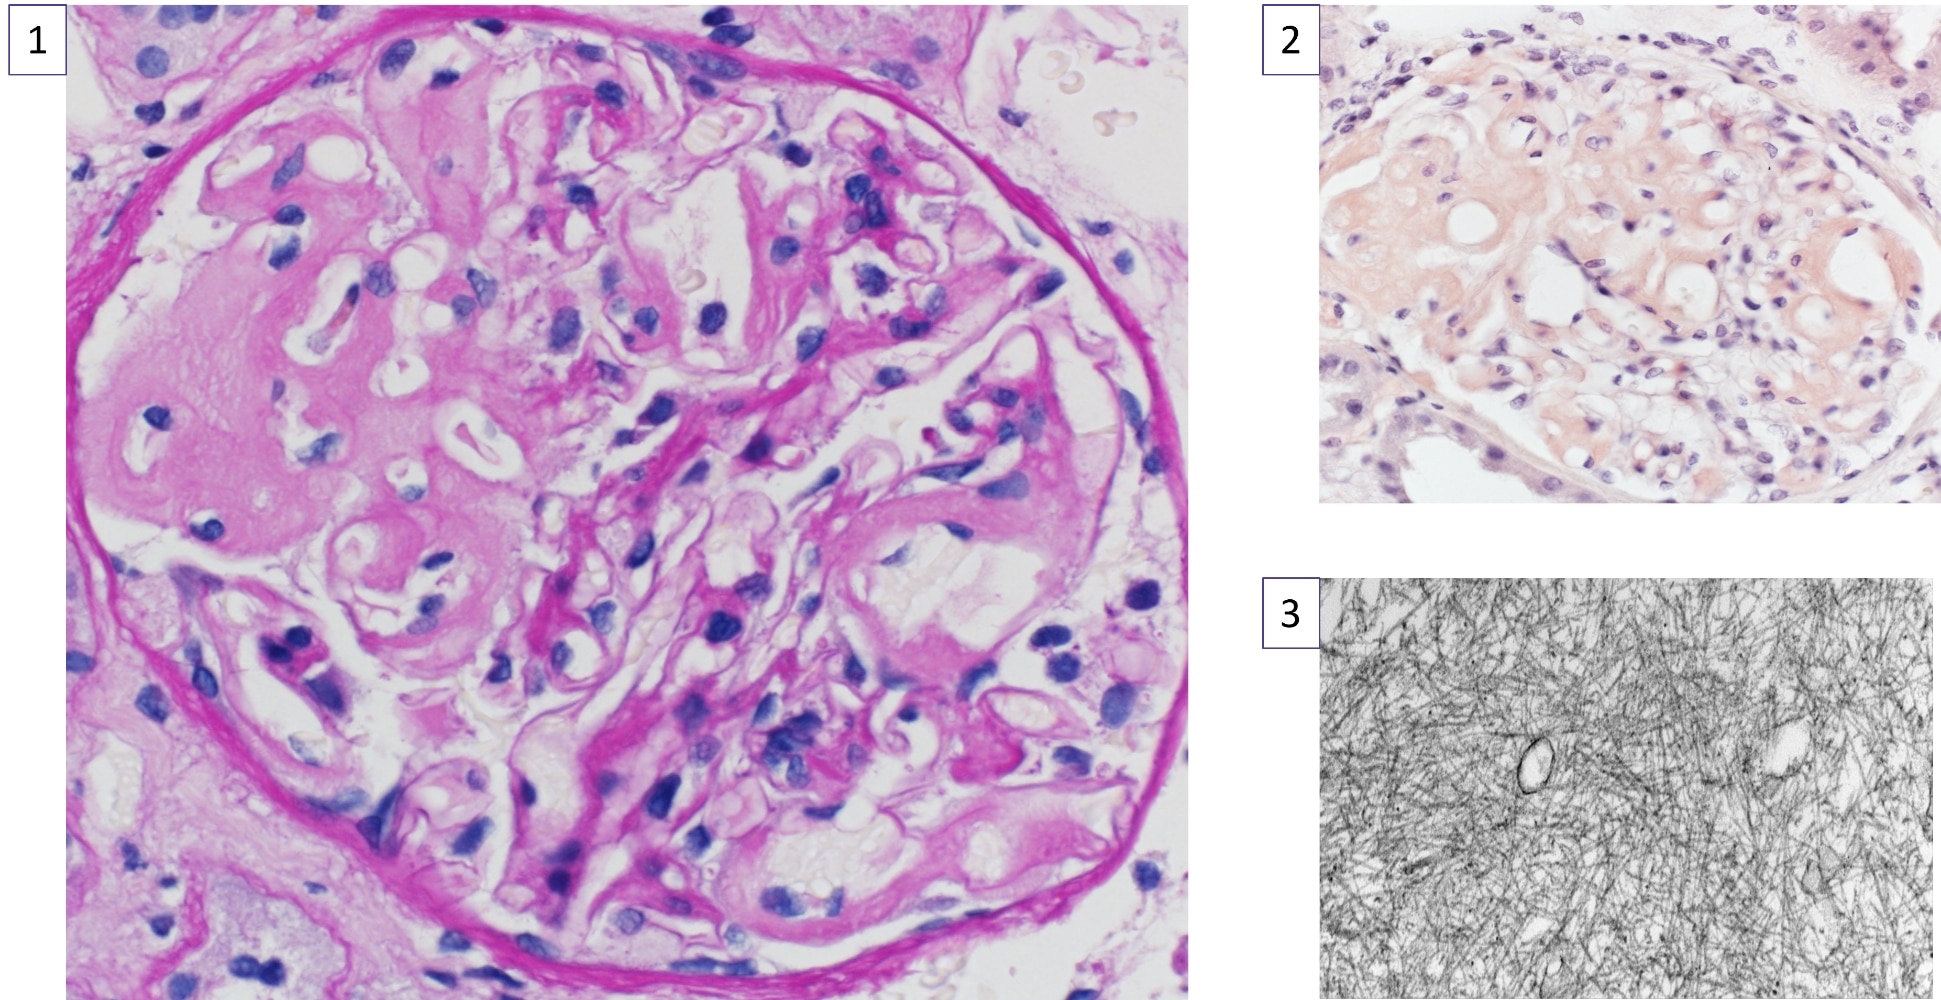

The Clinical Nephrology Section studies various kidney diseases, including membranous nephropathy and focal segmental glomerulosclerosis. The goal of our research is to better understand the evolution and outcomes of these kidney diseases and find treatments that may be more effective and less toxic.

Research Images